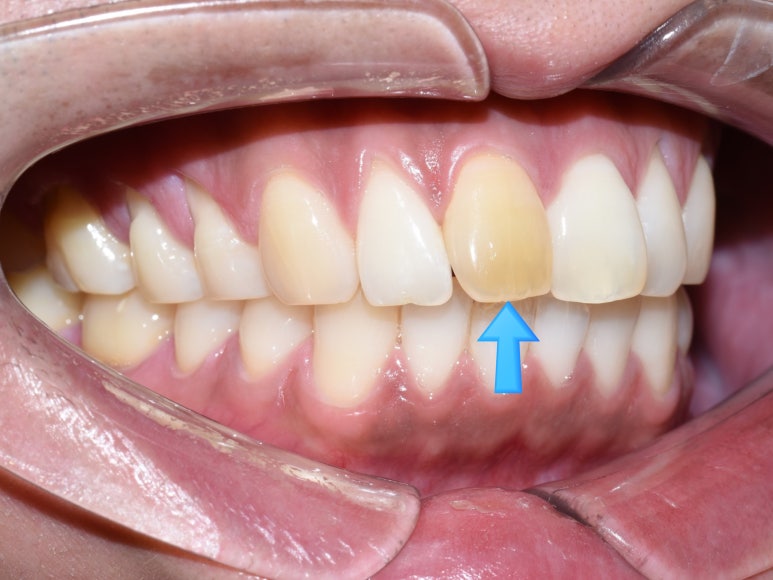

이렇게 앞니가 하나 , 하나만 변색되신 분들이 굉장히 많습니다.

앞니 한두개 변색되신 분들이 한국인 외국인 할 것 없이

부딪히는 외상으로 인해 변색이 생겼을 수도 있고

신경치료 후에 피치못하게 치아 변색이 생기는 분들도 계십니다.

보통 신경치료 후에는 대부분 기본적으로 크라운을 씌우게 되는데

간혹 앞니나 특수한 케이스에서 크라운을 씌우지 못한 경우에

변색이 온 후 크라운을 하겠다고 찾아오시는 분들이 많이 계십니다.

그런데,

교정을 하신 분들도 많다보니 그 크라운을 해야하는 앞니에

유지장치가 붙어있는 분들도 많으세요.

위의 사진에서 철사보이시죠?

화살표된 두개 앞니 치아 치료